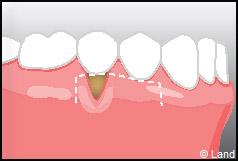

Les greffes de conjonctifs enfouis :

Destinées aux zones esthétiques, elles consistent à prélever la partie profonde du palais (site donneur).

Ce greffon est ensuite inséré sous la gencive au niveau de la récession (site receveur).